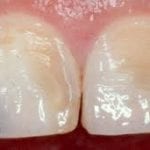

Enamel erosion can cause symptoms like tooth stains and sensitivity. Tooth enamel can’t be regrown. But you can prevent erosion from getting worse with dental treatment and by taking care of your teeth.

- cracks and chips

- gradual wearing of enamel, leading to clear, slightly translucent teeth